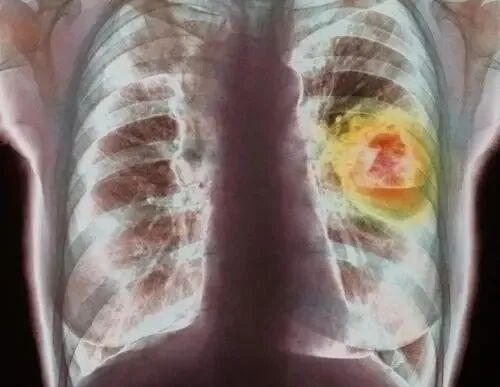

儿子火速赶回,带他去了省城的大医院。一查,竟然是肺癌中晚期,已经转移了,肿瘤压迫了上腔静脉。

03面部浮肿: 面部水肿是肺癌患者常见的表现之一,当肿瘤压迫到上腔静脉时,会阻碍静脉回流,导致面部、颈部水肿,甚至伴有皮肤发紫等症状。